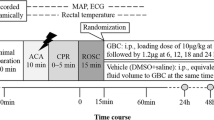

MR image analysis

In-house developed software (MATLAB ver. R2010a, Math Works Inc, Natick MA, USA) was used to calculate apparent diffusion coefficient (ADC) maps by fitting a mono-exponential model to the signal intensity of the images with different b-values, while T2-maps were calculated by fitting a mono-exponential model to the signal intensity of the images with different TE-values. The same software was also used to calculate DCE parameters using the average signal intensities within the region of interest specified below. The following DCE parameters were calculated based on the T1-weighted image series acquired during and after gadolinium-based contrast injection: relative signal intensity (RSI) 1.5 min after contrast injection, RSI 1.5min , area under the curve (AUC) during the five first min after contrast injection, AUC 5min and time to peak signal (TTP).

All MR images were visually evaluated with respect to morphological changes and with abnormal signal areas. In addition, Medical Image Processing, Analysis and Visualization software (ver. 5.3.4, Centre for Information Technology (CIT), National Institutes of Health (NIH)) (McAuliffe et al. 2001) were used for regions of interest (ROI) analyses of the image data. ROIs in the frontal, parietal and occipital cortex, hippocampus, putamen, thalamus and brain stem at the level of pons were drawn in the T2-maps (Fig. 1) and copied to the ADC-maps and T1-weighted images to ensure the same placement of ROIs in all image sets. Average voxel values in each of these regions were calculated and compared between groups. The same ROIs were also used to calculate DCE parameters, as described above. For the T1-weighted images used for manganese-enhanced MRI 1 week after the dive, ROI were also drawn in muscle areas lateral to the brain on both sides. Using the average signal intensity from muscle, the mean relative contrast (RC) was calculated in all the other ROI using the formula:

Acute MRI findings

Decompressed rats had a different time-curve for the dynamic contrast-enhanced MR signal than controls, with higher RSI (P = 0.017), a tendency towards longer time to peak (P = 0.11) and a larger area under the curve for the whole brain (P = 0.099) (Fig. 2). Region of interest based analyses of the dynamic contrast-enhanced MRI (DCE MRI) data that showed differences between decompressed and control animals in frontal cortex and thalamus. Decompressed animals had higher mean RSI (P = 0.023, Table 1) and a tendency towards higher TTP and AUC in the frontal cortex than control animals (P = 0.076 and P = 0.068, respectively). In the thalamus, AUC was higher among decompressed animals (P = 0.033, Table 1) with a tendency towards higher RSI and TTP (P = 0.068 and P = 0.104, respectively). For all other areas, there were no significant differences between the two groups.

Interestingly, the variation in all three parameters (RSI, TTP and AUC) was higher among decompressed animals than controls. There were no specific areas with increased signal in the post-contrast image compared to the pre-contrast image. The ADC-maps and T2-maps did not show any focal changes indicating pathology in neither the decompressed nor the control animals. Measurements of ADC and T2 in several brain areas showed no differences between the groups (Tables 2 and 3).

MRI 1 and 2 weeks after decompression

The T2-maps showed no signal abnormalities or morphological changes 1 or 2 weeks after the decompression. Region of interest based measurements of T2 showed higher T2 in the brain stem among decompressed animals than controls after 1 and 2 weeks, with the same tendency seen in thalamus (Table 3). There was also a similar reduction in T2 in both groups from time 0 to week 1, with a slight increase to week 2 (Table 3) which was related to the administration of manganese on day 1 after decompression. Visual inspection of T1-weighted images after 1 week showed similar manganese-enhancement in both groups, and region based analysis of the images did not show any differences between groups in relative contrast 1 week after administration of MnCl2 (Table 4).

No specific white matter abnormalities were seen on DTI and parameters such as fractional anisotropy (FA) (Fig. 3), mean, axial and radial diffusivity were not different between groups in the measured white matter structures (Table 5).